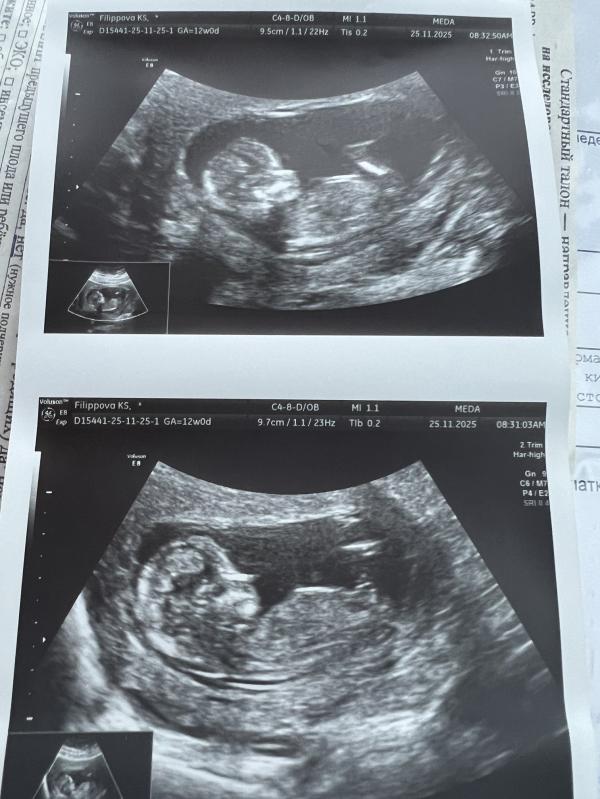

Первый скрининг пройден, жду кровь 🙏

По узи с малышом все хорошо тьфу тьфу и да 9/10 что это малыш, Эмилия Юрьевна отменяется))

Поздравляю) я тоже прошла, но мне не предположили пол) да и фоток не напечатали 😄 но разрешили сфоткать монитор)

😍 какое чудо